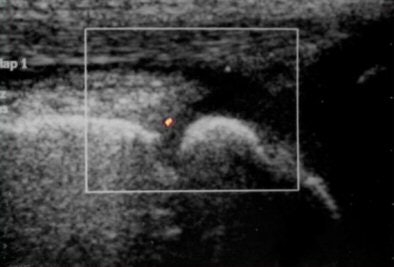

![]() |

| Baseline PDS of right knee reveals marked vascular signals. |

| Follow-up images of the same patient at the end of the second (above) and sixth (below) month after therapy demonstrate significant decrease in vascularity. |